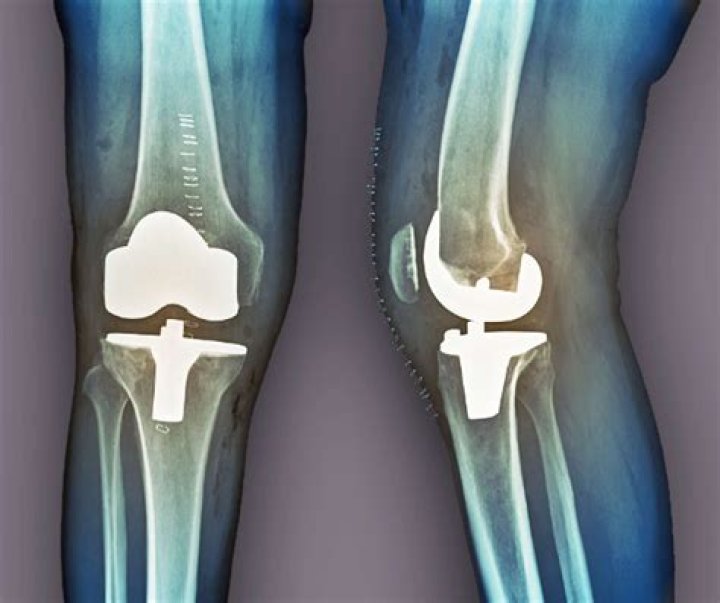

Read JournalA knee replacement is major surgery, so is normally only recommended if other treatments, such as physiotherapy or steroid injections, have not reduced pa...